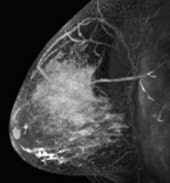

| A 41-year-old patient with invasive ductal carcinoma, grade III, studied while undergoing neoadjuvant chemotherapy treatment. MRI was performed using contrast-enhanced 3D fast gradient-recalled echo pulse sequence (TR/TE, 8/4.2; flip angle, 20°; 18-cm field-of-view, 2-mm slice thickness, 256 x 192 acquisition matrix). Patient presented with 71 cm3 (6.2-cm diameter) tumor and experienced increase in MRI tumor volume throughout treatment (28% overall increase). At surgery, 8 cm of residual disease and nine involved lymph nodes were identified. Patient experienced disease recurrence eight months after surgery. Maximum intensity projection (left) with corresponding tumor volume segmentation for representative sagittal slice (right) acquired before initiation of chemotherapy. Partridge SC, Gibbs JE, Lu Y, Esserman LJ, Tripathy D, Wolverton DS, Rugo HS, Hwang ES, Ewing CA, and Hylton NM, "MRI Measurements of Breast Tumor Volume Predict Response to Neoadjuvant Chemotherapy and Recurrence-Free Survival" (AJR 2005; 184:1774-1781). | |